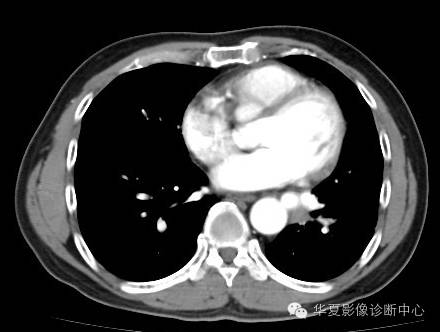

| 影像表现及分析: | 影像表现:定位左下叶;左下叶体积缩小,整体密度增高,支气管分布正常,其内见血管增多,但是走形正常,未见杂乱、迂曲的血管影;血管连向肺门下方软组织密度结节灶,结节与主动脉分界不清,增强后,见降主动脉发出异常粗大血管供血整个左下叶,左下肺动脉细小。 |

异常体动脉供应正常下肺基底段完整含义为起源于降主动脉的异常动脉供应下肺基底段,而基底段支气管树和肺实质正常,同时基底段肺动脉缺如或狭窄【大部分缺如(完全型),部分狭窄(不完全型)】;95%以上累及左下肺,因此也称为异常体动脉供应正常左下肺基底段。 病因尚未明确,可能是胚胎发育时期供应肺芽的背主动脉原始小分支退化不全,与肺实质形成异常连接,并影响肺动脉与肺血管床连接而导致此部位肺动脉发育不良,而支气管、肺组织的发育未受影响。本病的病理生理基础为左向左的分流,体动脉供应的肺组织充血,体循环的高压可增加肺血管床的压力和左心负荷,同时也增加肺循环量和压力而增加右心负荷,导致各种临床症群。本病可无临床症状,部分患者可有咯血、呼吸道感染、呼吸困难、充血性心力衰竭。 影像表现:左肺下叶体积缩小,整体密度稍增高,支气管树走形、分布正常,血管增多、稍增粗;增强后显示左下肺动脉幼小,甚至不发育;下叶由主动脉发出的粗大血管供血。 |